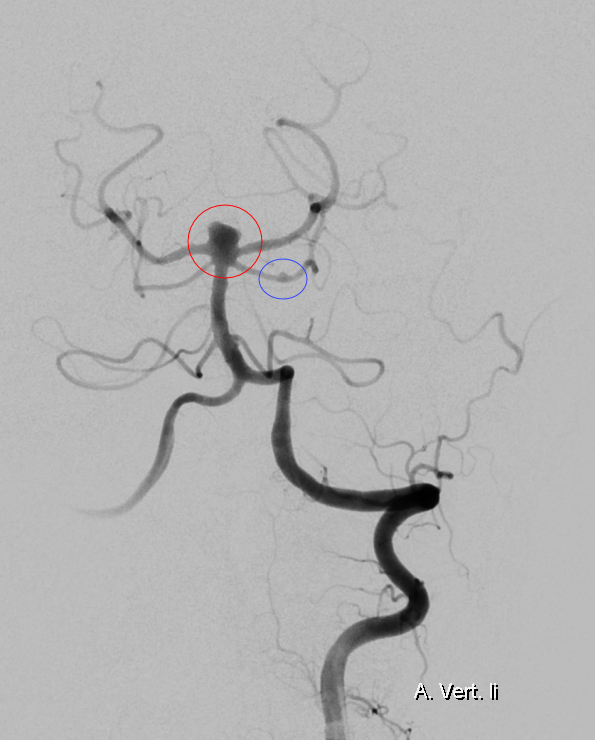

Abbildung

Bildgebung

Der Goldstandard zur optimalen Darstellung der Arteria cerebelli superior ist die digitale Subtraktionsangiographie.

Aneurysma

Aneurysmen der Arteria cerebelli superior sind äußerst selten und können je nach Fall mikrochirurgisch als auch endovaskulär behandelt werden[^3].